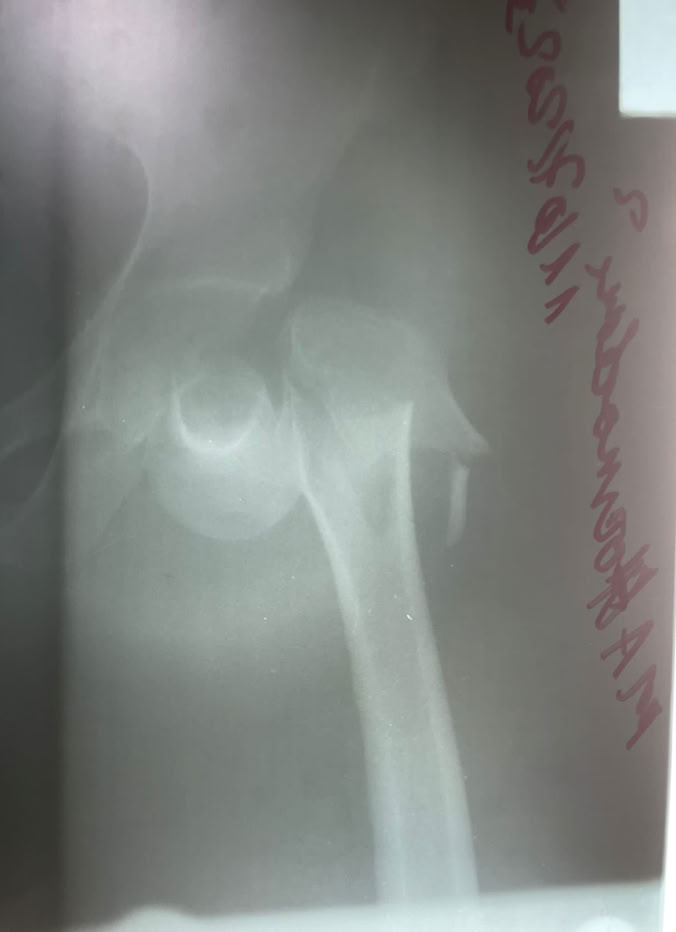

Las sesiones quirúrgicas se han podido dividir entre todos los integrantes pudiendo llevar a cabo a dos quirófanos varias cirugías entre ellas un caso complejo de fractura luxación de cadera con tibia bifocal homolateral consecuencia de los tan frecuentes y graves accidentes de moto.

En la consulta se fue fraguando lo que iba a ser nuestro quirófano a lo largo de la estancia pudiendo comprobar que la situación endémica de fracturas de tibia en todas sus modalidades continua sin cambiar. En total se han realizado 23 cirugías entre las que cabe destacar el caso anterior, ademas de 5 seudoartrosis de tibia, dos fracturas de fémur, una fractura luxación Lisfranc, de radio, seudoartrosis de humero y varios casos de cirugía de mano y miembro superior pues nos acompañaba el Dr. Galan . Ademas se han realizado varias limpiezas quirúrgicas de osteomielitis, osteítis y movilización séptica de una PTC, injertos de piel y un solo caso de ortopedia infantil de un Blount, realizado por el Dr. Nges. Poco a poco la autonomía para la resolución de los casos es mayor por parte del equipo local sin dejar de introducir nuevas técnicas como el enclavado humeral.